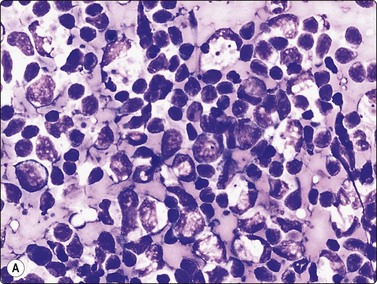

image image

Fig. 5.2 Small cell anaplastic carcinoma

Dispersed malignant cells with dense chromatin, irregular nuclear contour, nuclear molding, inconspicuous nucleoli and cytoplasm; note irregular cytoplasmic (B) and nuclear fragments in the background representing tumor necrosis (A and B) (MGG, HP).